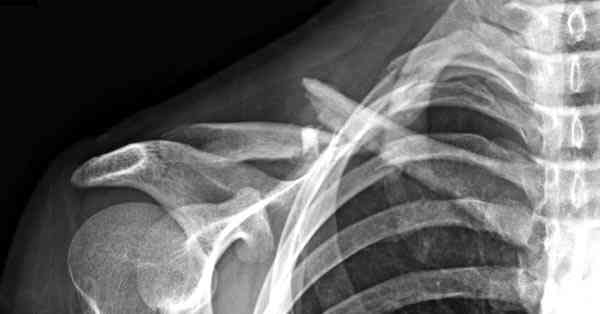

Второй случай тоже недавно оперирован по поводу

ложного сустава, в марте травма, через 4.5 половиной

операция..